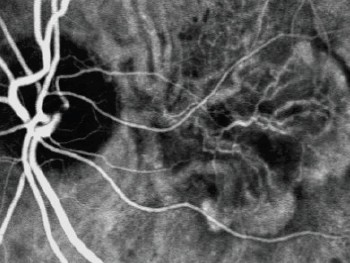

A angiografia é realizada com a injeção do corante Indocianina Verde. Associado à Angiografia Fluoresceínica e a Retinografia, complementa esses exames, auxiliando nos diagnósticos que possam estar inconclusivos nos exames prévios. É indicado na avaliação de doenças que acometem a circulação coroideana, que fica atrás da retina, avaliando as membranas neovasculares na Degeneração Macular Relacionada à Idade (DMRI), coroidopatia serosa central, coroidopatia polipoidal, entre outras doenças. Pode ser utilizado também para medir as membranas que serão tratadas com Terapia Fotodinâmica (PDT).

Da mesma forma que é realizada a Angiografia Fluoresceínica, o contraste é injetado em uma veia do antebraço ou do dorso da mão, e fotografias digitais são tiradas do fundo de olho dos pacientes, com as pupilas previamente dilatadas. A duração do exame é um pouco mais demorada, em torno de 20 a 30 minutos, para que o corante possa circular no olho e as imagens captadas.